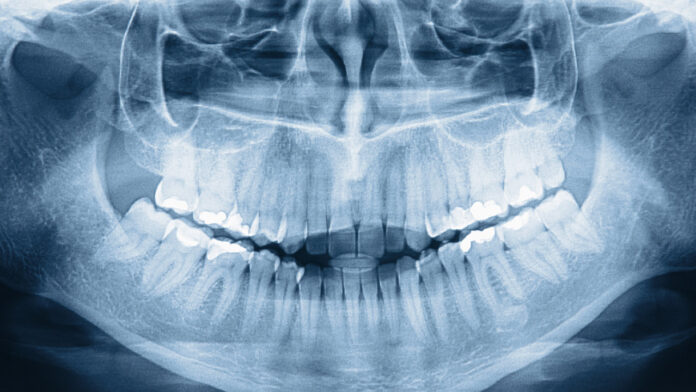

Standart bir insanda 32 diş bulunurken, 42 yaşındaki Prathab Muniandy tam 42 dişiyle dünya rekoru kırdı. Bir aile yemeğinde tesadüfen fark edilen bu durum, tıp dünyasının “hiperdonti” dediği nadir bir mucizeyi işaret ediyor. Peki, sizin ağzınızda fazladan diş saklı olabilir mi?